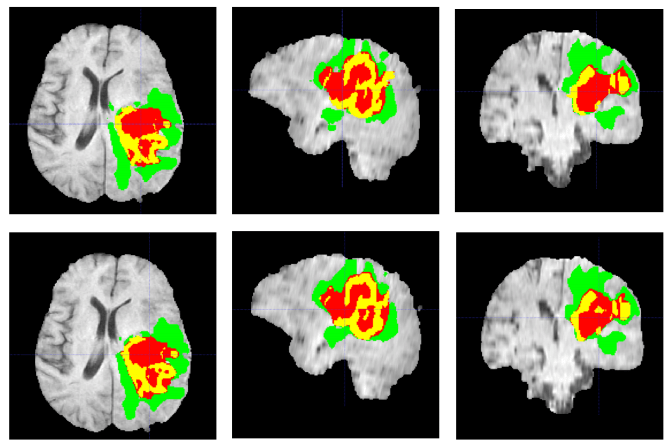

با این وجود هنوز فرصت پیشرفت در روشهای کنترل بیماریهای مختلف به خصوص سرطان وجود دارد. تشخیص به موقع سرطان گامی مهم در درمان موثر این بیماری است، زیرا شانس زنده ماندن فرد مبتلا را مشخص میکند. بین انواع مختلف سرطان گلیوما اهمیت زیادی دارد؛ زیرا شایعترین تومور مغزی اولیه است و سطوح تهاجمی مختلفی دارد. یکی از روشهای رصد این بیمار استفاده از MRI است که چشمانداز بصری دقیقی از تومور و بخشهای مختلف آن فراهم میکند و در نتیجه رصد دقیق مکان، شکل و ویژگیهای منطقهای آن ممکن میشود.

در همین راستا گروهی از محققان ایرانی در داخل و خارج از کشور به نامهای آرمین بنکدار، نسترن شکوریفر از دانشگاه خواجه نصیرالدین طوسی و مجید سلطانی و کامران راحمیفر از دانشگاه واترلو کانادا رابطه بین حداکثر قطر مناطق فرعی تومور و شاخصOS در موارد ابتلا به گلیوبلاستوم را بررسی کردند. آنها برای این منظور از مخزن دادههای MRI بیماران گلیوبلاستوم استفاده و آنها را براساس وضعیت جراحی برداشت تومور به ۲ گروه «برداشتن کل ناخالصی» (GTR) و برداشتن میزان نامشخص (NA) تقسیم کردند. در مرحله بعد آنها از یک الگوریتم خاص استفاده کردند و حداکثر قطر مناطق فرعی تومور را تخمین زدند. سپس از الگوریتمهای ماشین یادگیری برای بررسی رابطه بین حداکثر قطر مناطق زیرمجموعهای و نرخ زنده ماندن بیمار استفاده شد. نتایج مدلهای پیشبینی تک متغیره نشان داد که حداکثر قطر نواحی اطراف تومور با میزان بقای بیمارانی که میزان برداشت تومور آنها ناشناخته است، ارتباط دارد.